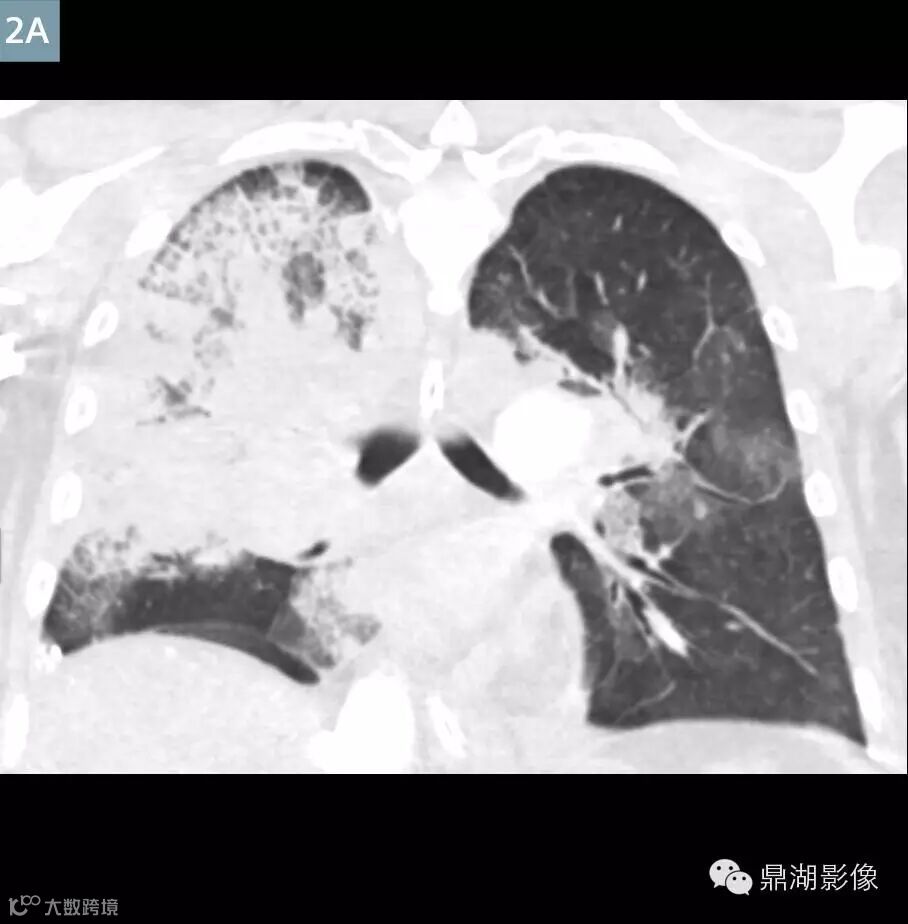

Coronal contrast-enhanced MPR (Fig. 2A) and VRT (Fig. 2B) image at the level of the pulmonary hila: Extensive right lung consolidative opacities represent pulmonary infarction.

肺动脉CTA显示新的多发性肺栓塞和右动脉完全闭塞(图1)。左下叶肺动脉和静脉灌注一直持续(图3)。存在广泛右肺动脉梗塞(图2)。上腔静脉,右心房,右心室充满造影剂,造影剂回流进入肝静脉和下腔静脉(图5A)。主肺动脉CT值衰减大于250亨氏单位,这可以让医生确定扫描的诊断质量。ECMO系统和主动脉的分支未显影,体现了良好的团注时间(图4)。